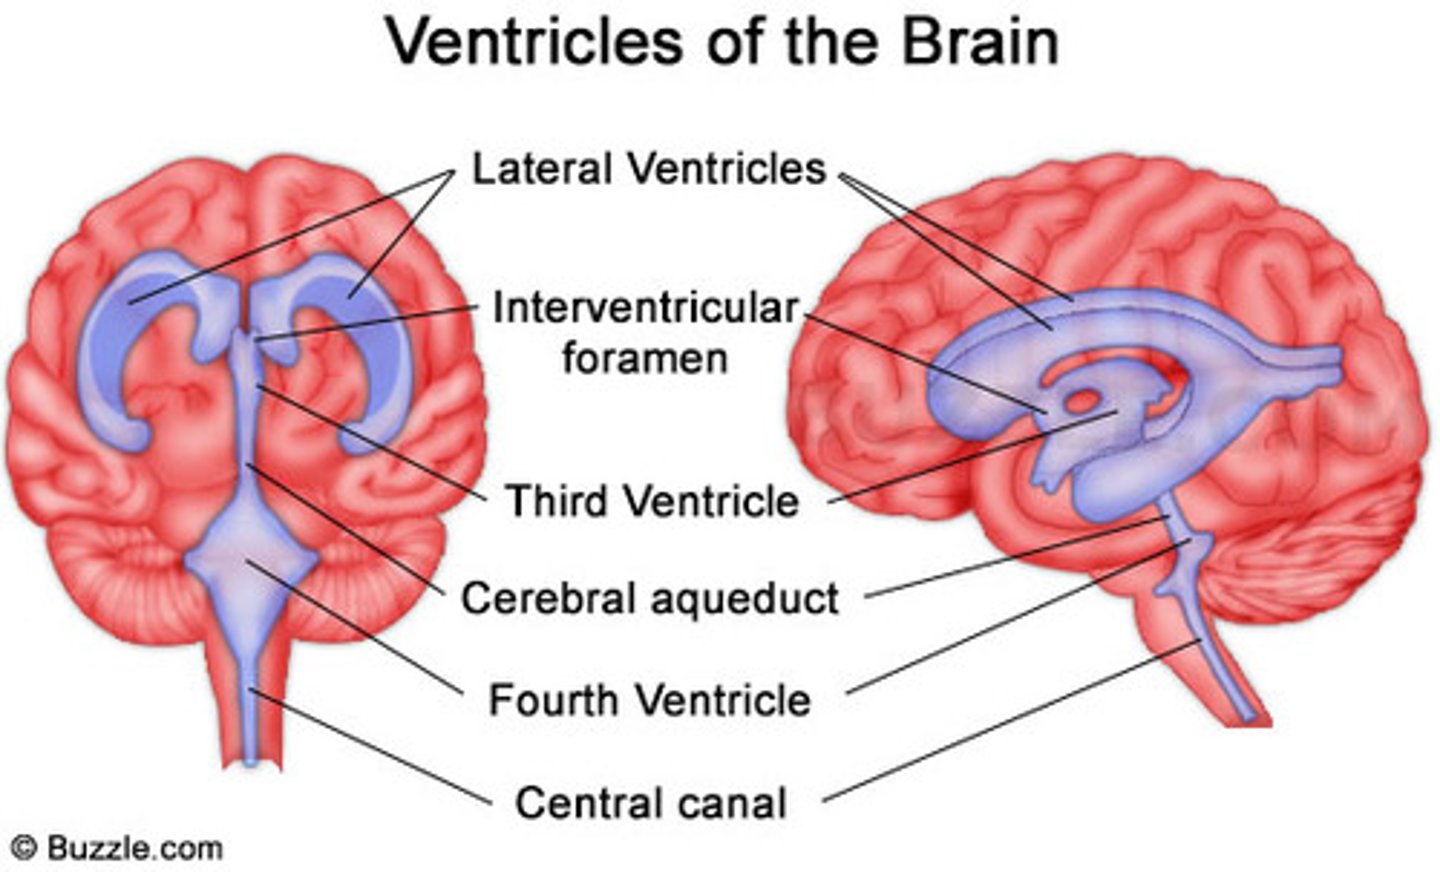

The opening of the neural tube become

Ventricles

4 Chambers within the brain,

Filled with Cerebrospinal Fluid,

Continuous with each other and with the central canal of the spinal cord

4 Chambers within the brain,

Filled with Cerebrospinal Fluid,

Continuous with each other and with the central canal of the spinal cord

Ventricles

1) Right & left lateral ventricles:

-Anterior, Posterior & inferior horns

2) 3rd Ventricle, Cerebral aqueduct, 4th ventricles

4) Apertures (Narrow openings) into subarachnoid space of spinal cord

Anterior Horns

Posterior Horns

Inferior Horns

3rd Ventricle

4th Ventricle